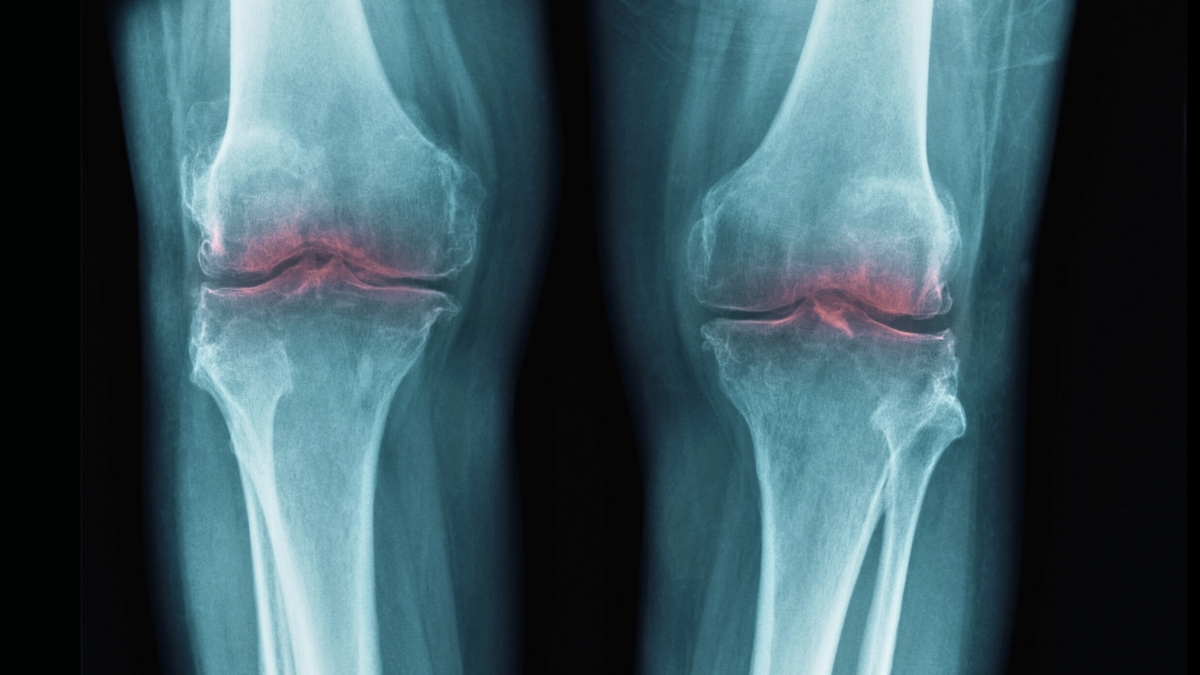

A study in mice by researchers from Stanford University has traced the loss of cartilage that comes with aging to a single protein, pointing to treatments that may one day restore mobility and ease discomfort in seniors.